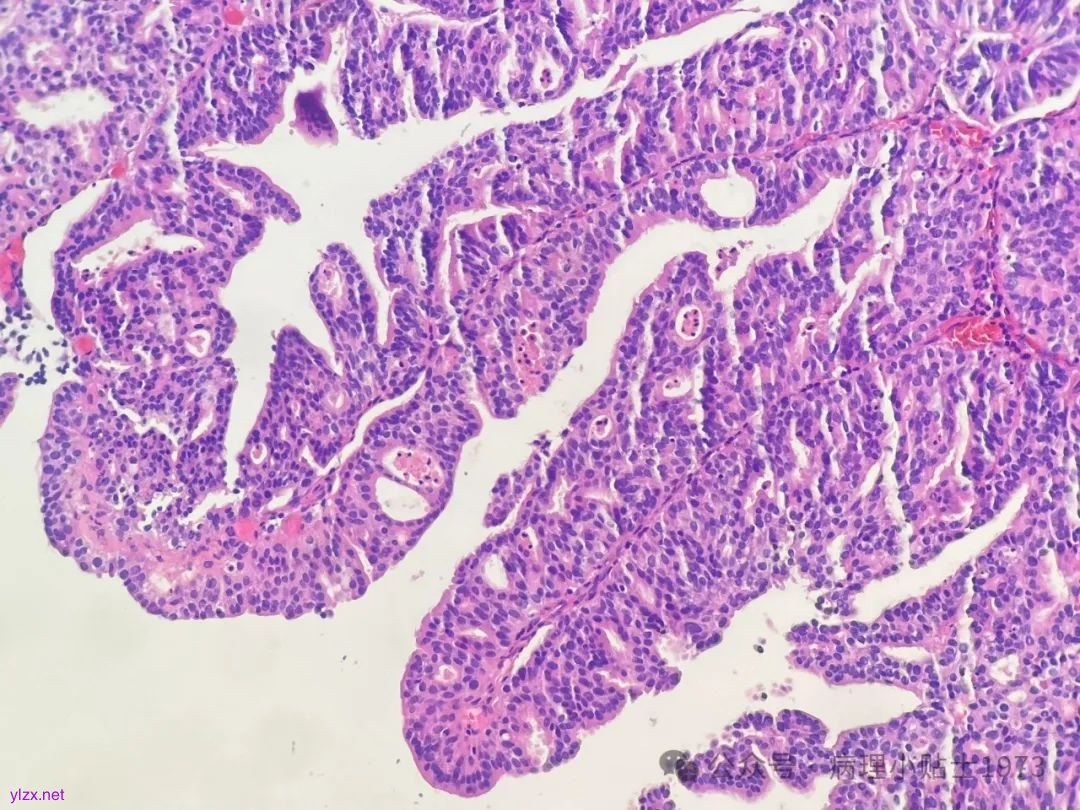

尿路上皮癌的诊断标准大家并不陌生,尿路上皮癌除了有很多组织学亚型,还可出现多种变异型(异向分化):包括伴鳞状分化、腺样分化、滋养细胞分化和苗勒型分化。

问题一:本病例出现了显著的腺性分化,不要误诊为单纯的腺癌。仔细寻找,仍然可以见到复层排列的经典尿路上皮癌成分。

有研究指出:伴腺样分化的尿路上皮肿瘤常是高级别,低级别尿路上皮增生性病变伴腺样分化常常不是肿瘤,可能是腺性膀胱炎或旺炽性腺性囊性膀胱炎。